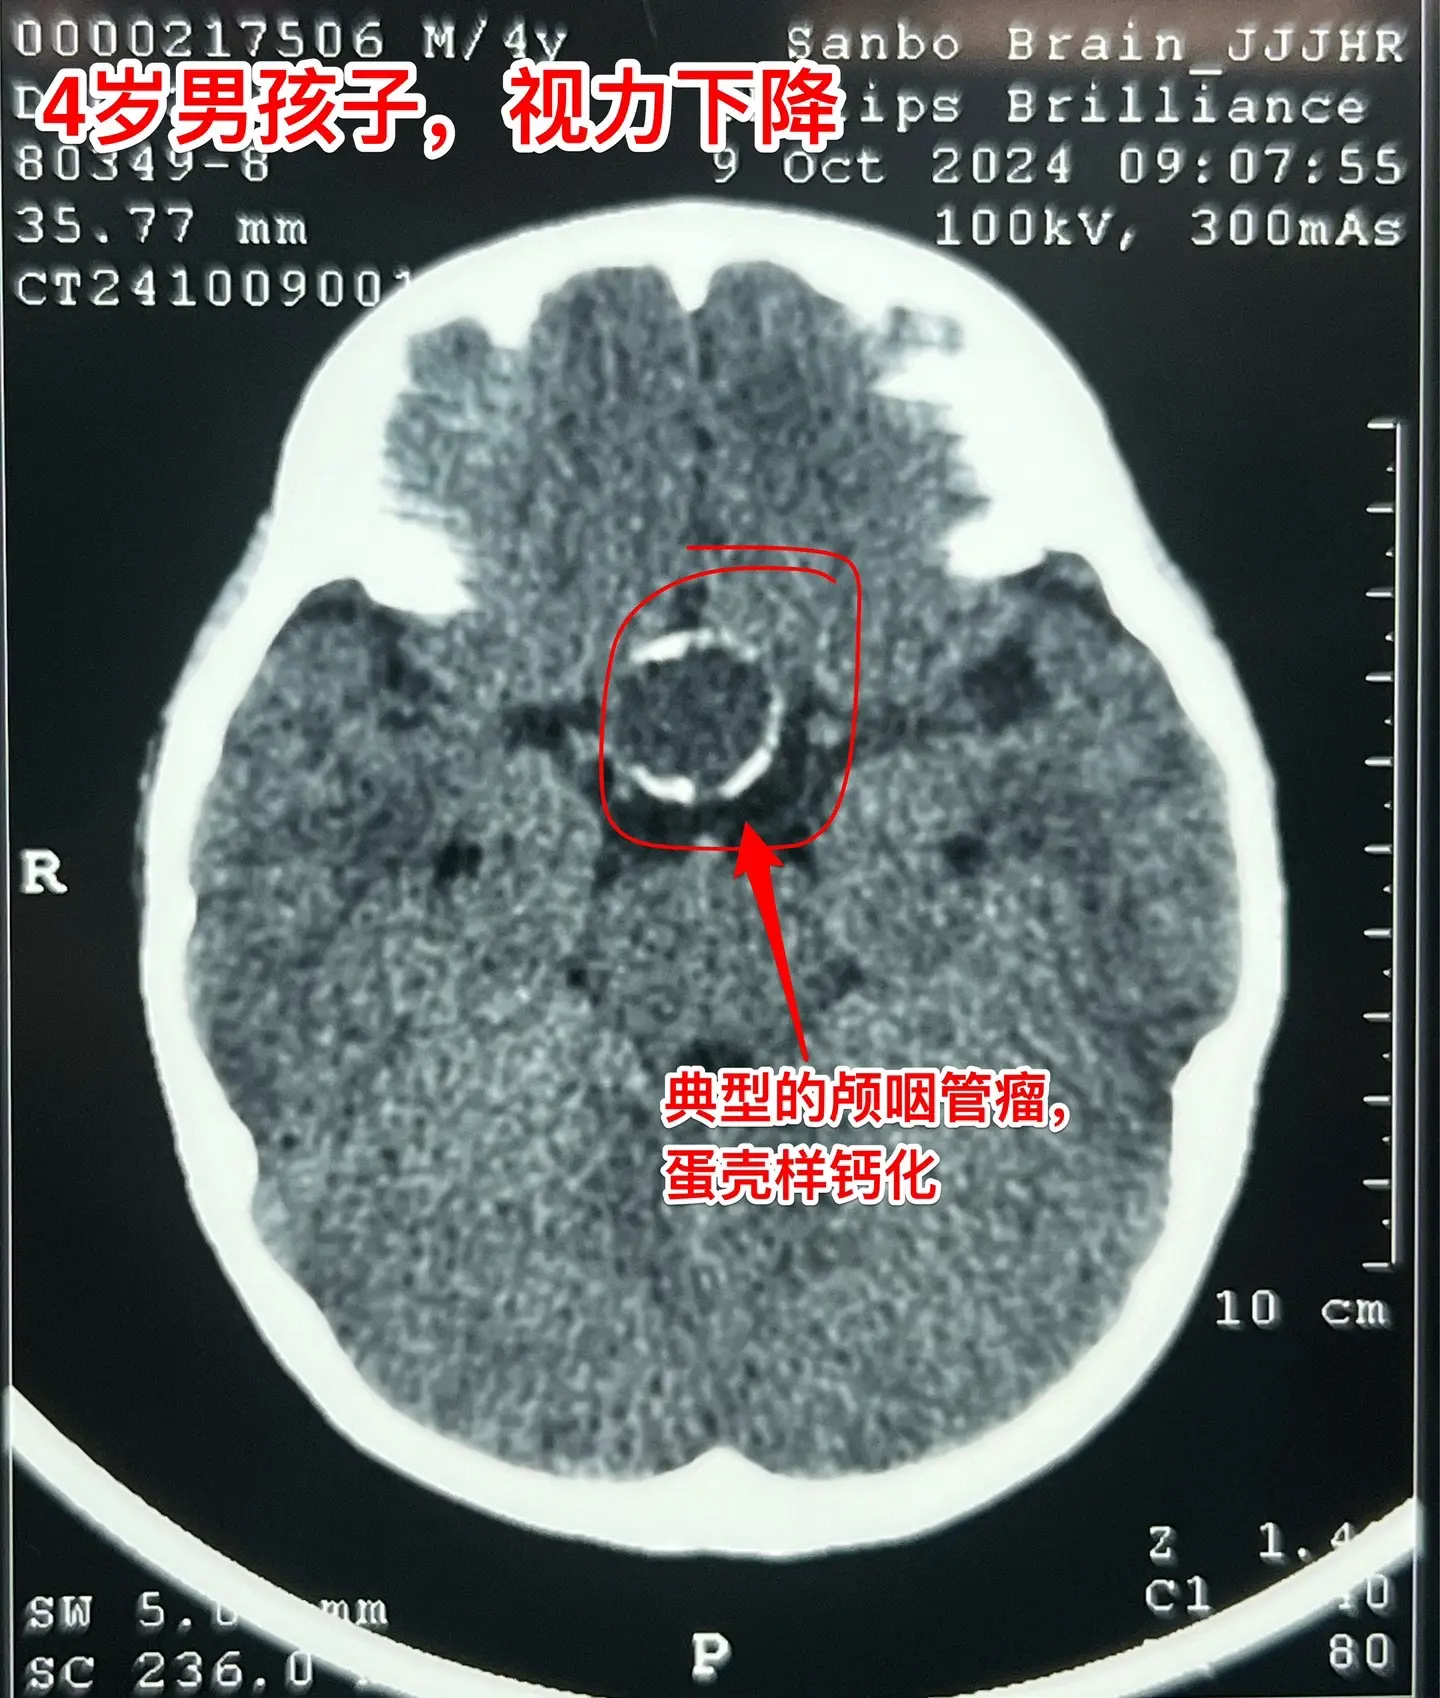

一天完成两个颅咽管瘤手术几乎成了常态。今天的两个颅咽管瘤手术,强度很大哦! 1,4岁男孩子,视力下降。典型的造釉细胞型颅咽管瘤,属于鞍隔下颅咽管瘤。开颅手术将颅咽管瘤完全切除,垂体大部分保留,垂体柄保留,下丘脑保护完好。这样的结果我们很满意! 2,35岁女性,经鼻手术后颅咽管瘤复发,视力下降。是乳头型颅咽管瘤。肿瘤与视交叉粘连很紧,手术分离难度大,最终得到完全切除。